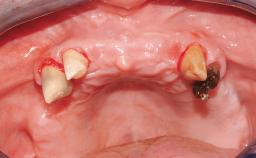

A healthy 31-year-old female patient presented with a failing maxillary left lateral incisor crown. The crown regularly loosened, and the remaining tooth was neither restorable nor rational to treat. The patient had a high smile line, a medium soft tissue biotype with a compromised mesial papilla (shorter than the contralateral one), and a horizontal scar in the buccal soft tissue as a result of past periapical surgery.

Timing of placement Immediate Placement (extraction sockets) (Type I)

Socket walls Intact

Thickness of buccal wall less than 2 mm

Anticipated residual defect after implant placement 2 mm or less